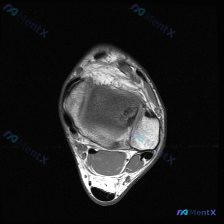

今天整理了一个很有代表性的读片矛盾病例,跟大家分享一下思路。 病例基本信息 这是一张踝关节MRI-T1序列的轴位图像,临床提示要找「软骨异常」。我们先看对这张图像的基础读片结果: 1. 骨骼:胫骨远端、腓骨远端、距骨形态完整,骨髓信号均匀,没有异常信号改变 2. 关节:胫距关节间隙正常,没有异常积液...